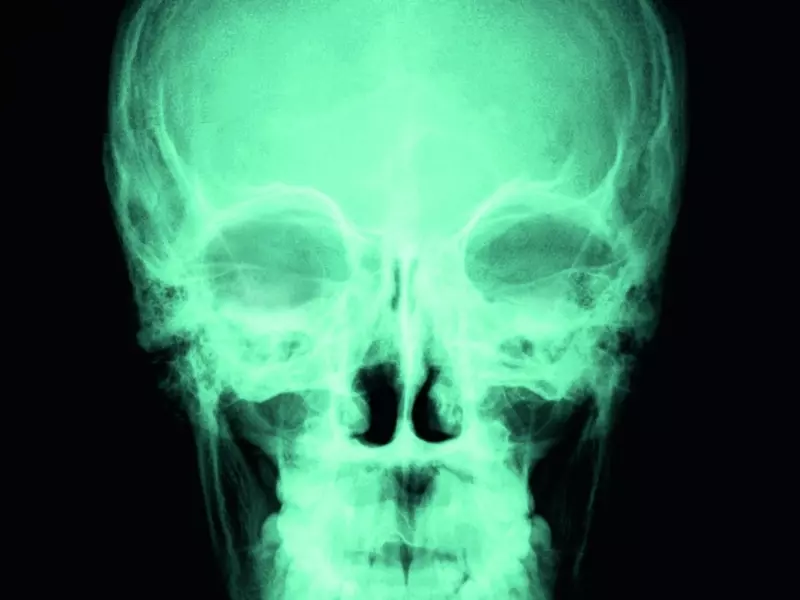

Nowe spojrzenie na drenaż obszaru czaszki i mózgu – perspektywa osteopatyczna

Na podstawie wyników najnowszych badań dotyczących płynu mózgowo-rdzeniowego i drenażu obszaru mózgu opisano możliwe podejścia pracy osteopatycznej, takie jak techniki dla żył szyjnych i splotu podstawnego, drenażu zbiorników mózgu, techniki pompażu czaszki, drenażu głębokich węzłów szyjnych, techniki dla opony twardej, usprawniania pompy limfatycznej, uwalniania kompleksu szczytowo-potylicznego, osteopatycznego drenażu limfatycznego, drenażu nosa, oczu i uszu oraz nerwów czaszkowych i nerwów szyjnych rdzeniowych górnych.